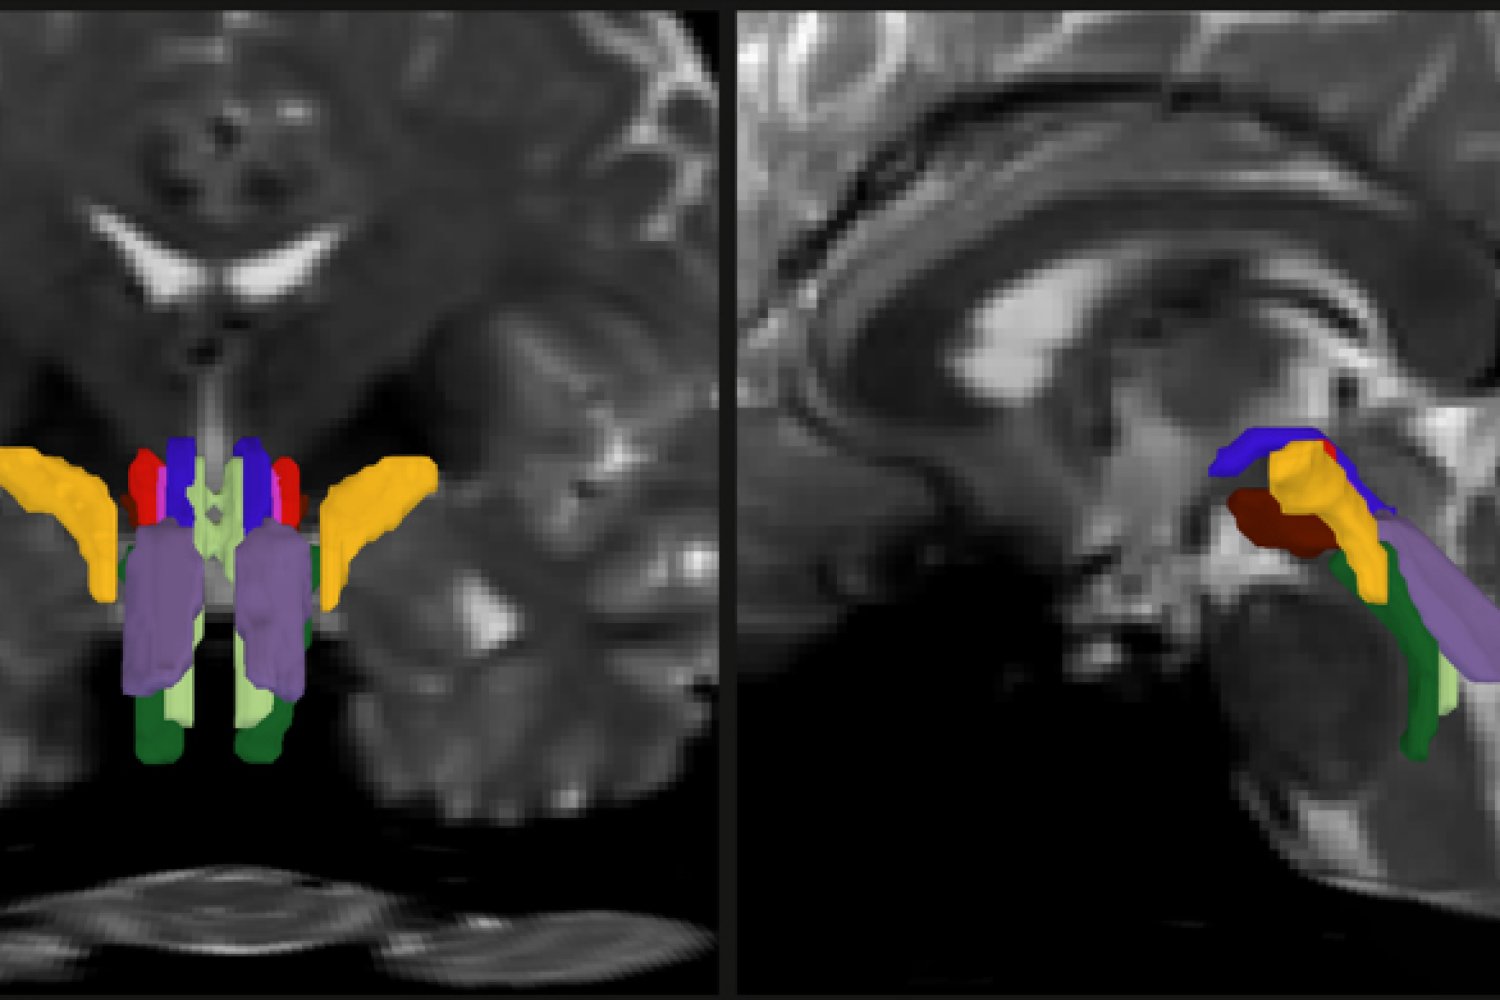

- AI-Driven Segmentation: BSBT uses advanced algorithms to visualize eight distinct fiber bundles in the brainstem.